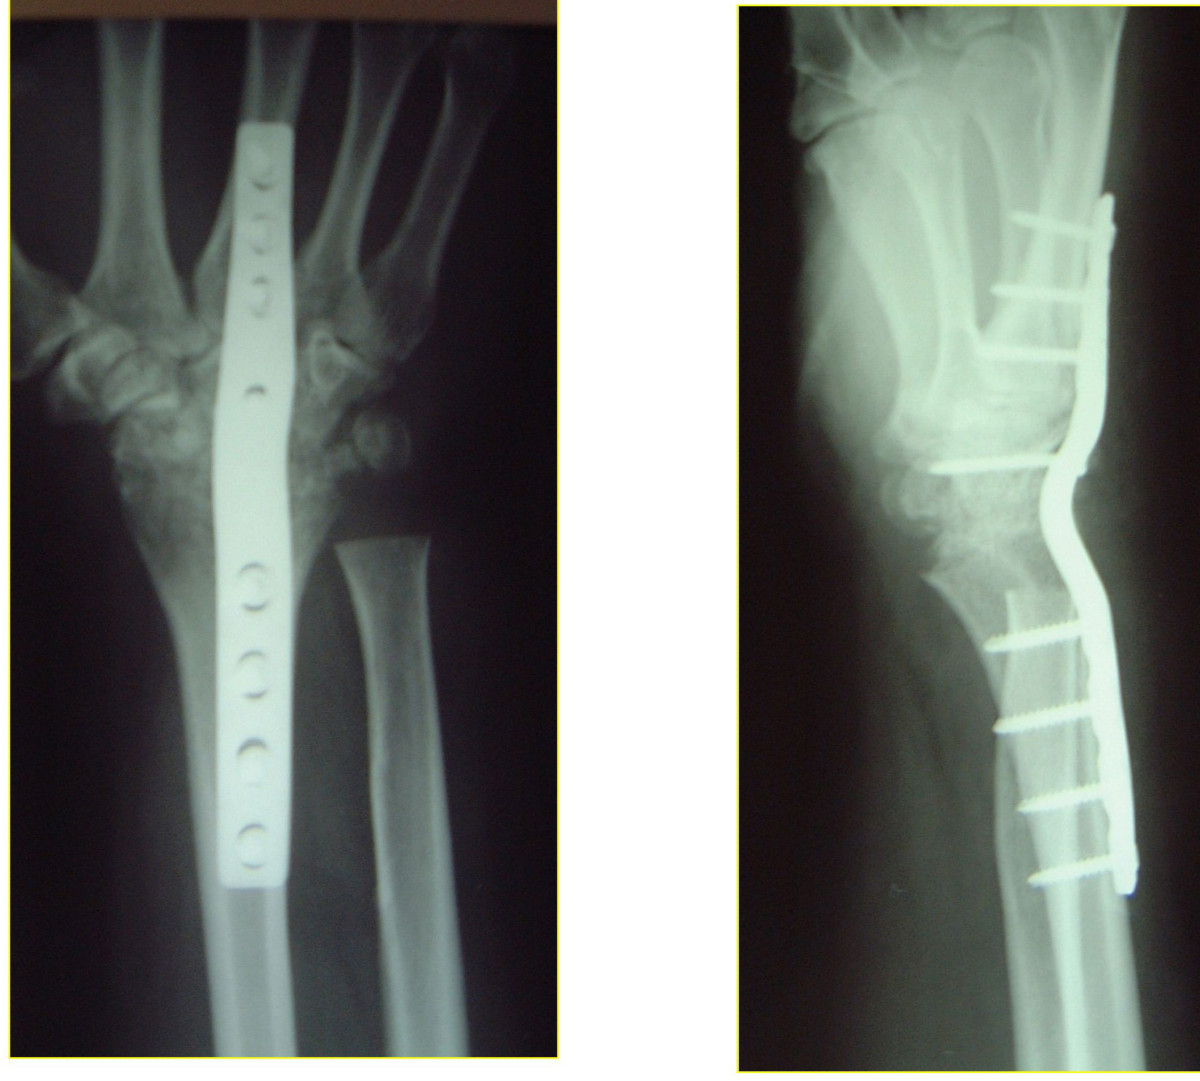

photos of wrist fusion

Plain radiographs of the left wrist following operative fixation. a …